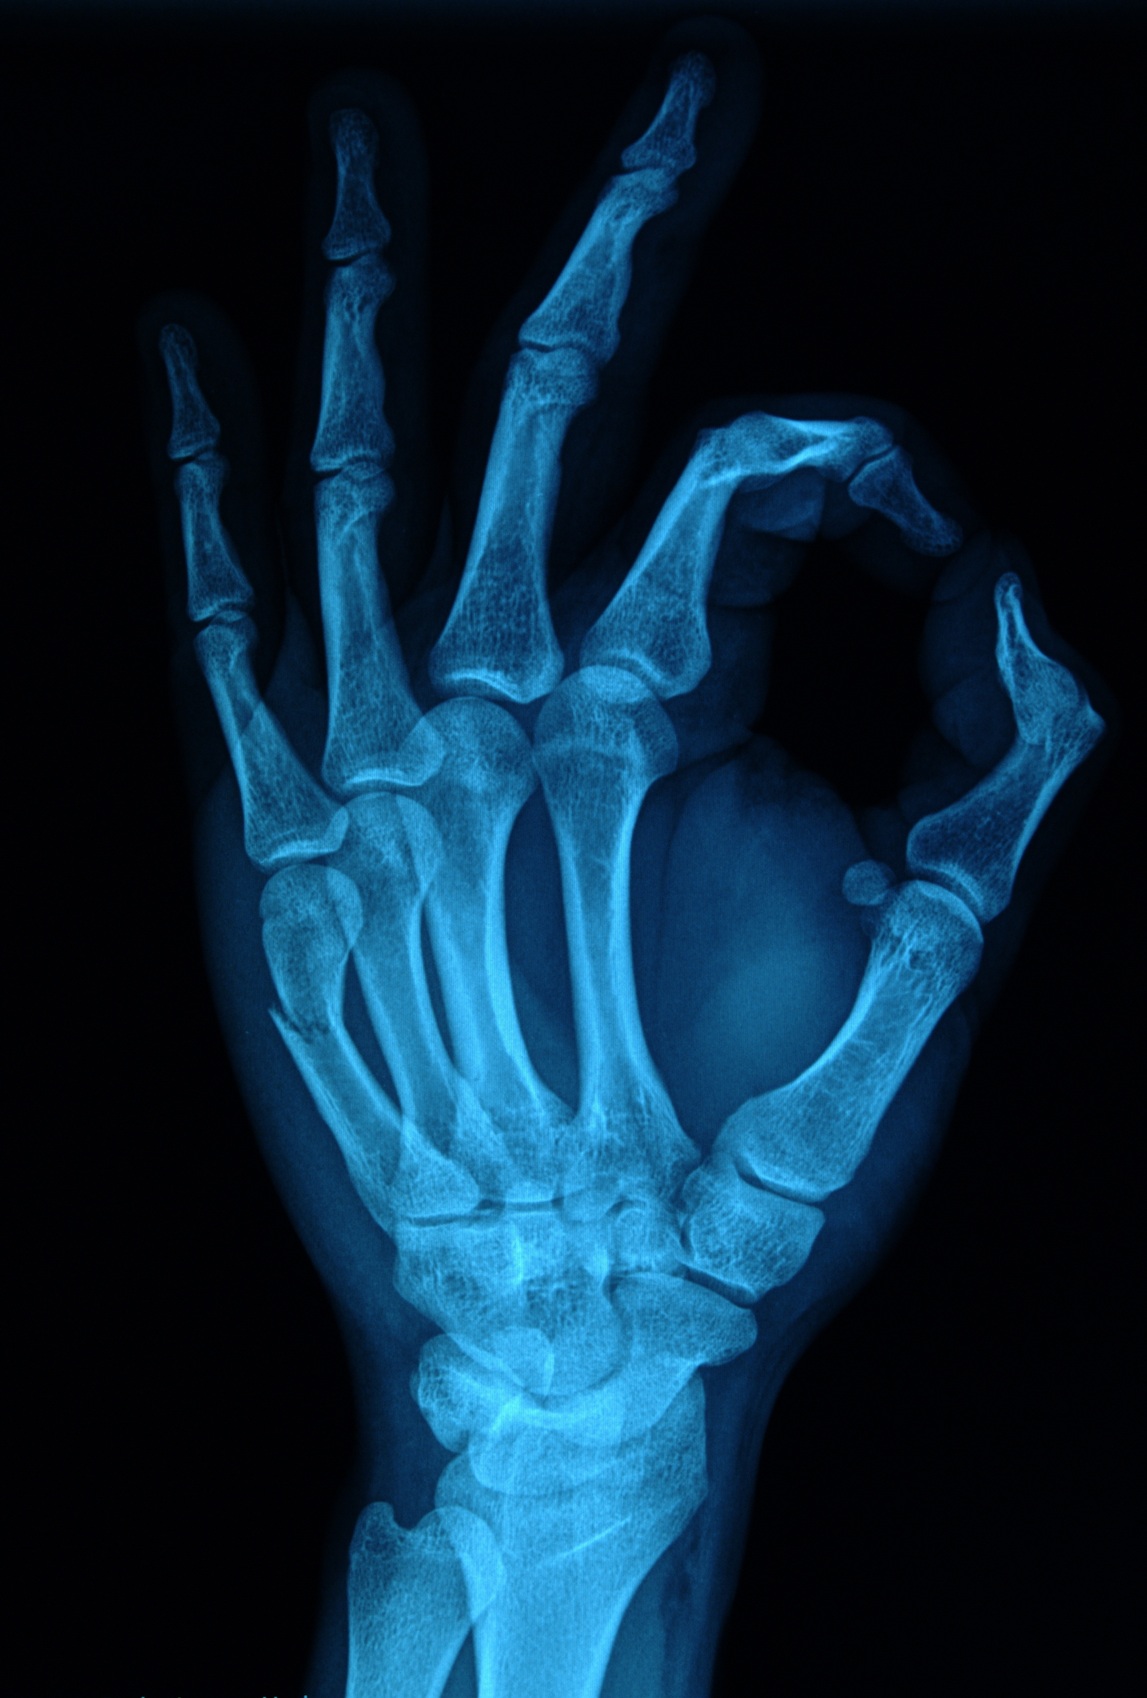

Standardem w diagnostyce jest oczywiście zdjęcie rentgenowskie (RTG) w co najmniej dwóch projekcjach. Pozwala ono ocenić ułożenie kości i wykluczyć złamania trzonów paliczków. Jednakże, anatomia dłoni jest skomplikowana, a drobne pęknięcia w obrębie stawu mogą być niewidoczne na klasycznym rentgenie. Dlatego, w przypadku wątpliwości klinicznych lub podejrzenia skomplikowanych uszkodzeń wewnątrzstawowych, może być wykorzystywana także tomografia komputerowa. To badanie pozwala z niezwykłą precyzją zobrazować strukturę kostną 3D i wykryć nawet najmniejsze fragmenty kostne oderwane wraz z więzadłami, co ma kluczowe znaczenie dla planowania dalszego leczenia i ewentualnych wskazań operacyjnych.